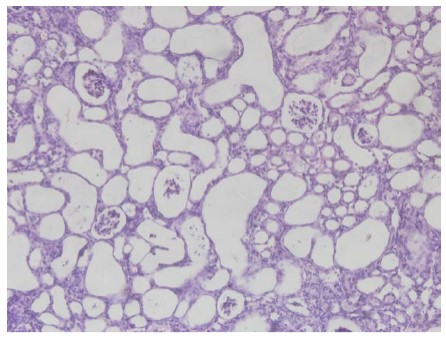

研究发现,化合物JK1303在500mg/kg剂量下已能引起小鼠的死亡和体重增长减缓,且在高剂量下毒性更为显著。对小鼠按照1000毫克/公斤剂量进行单次给药给予JK1303,14天后小鼠肾小管严重坏死,解剖发现其肾小管出现大量空泡。